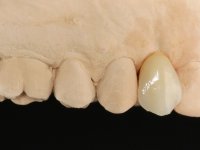

The proposed treatment results from the limitations imposed by the patient, who refused an orthodontical pull of the canine into the edntulous space, and was unwilling to extract the impacted canine and place an implant in the zone of 1.3. Thus, the confection of a Maryland Bridge was proposed, with a Zr infrastructure and two retainers. The mesial retainer would be bonded to the palatal face of the tooth 1.2 and the distal retainer was to be bonded to the palatal wall of tooth 1.4.

To define the dental zone to be covered by the Maryland bridge retainers, the patient was asked to perform maximum intercuspidation movements, and the contact points were marked with articular paper. Tooth preparation of the interproximal surfaces was made, to create a prosthetic insertion axis. It was sought that the mesio-distal diameter at the incisal level was equal to the diameter mesio-distal at the cervical level, that is to say, the interproximal walls were parallelized. Tooth preparation was done with fine grain diamond drills, and later polishing was done with abrasive discs. Color information was collected even before confection of the impression, to avoid dehydration of the arcade. Definitive impression was made using wash technique impression with silicone of heavy and regular consistency, both with fast setting, and a working plaster model was prepared in the lab. A laboratory scanner was used to scan the working model, and later, the infrastructure for the Maryland bridge was made using a CAD-CAM process. Ceramic was placed on this subframe. A ceramic adhesive was applied to the internal surface of the wings and connectors, which would enable bonding to the adjacent teeth. The adhesive bridge was bonded in the mouth following the conventional bonding technique. After bonding, the protrusion and laterality movements were carefully checked to avoid undesirable contacts.